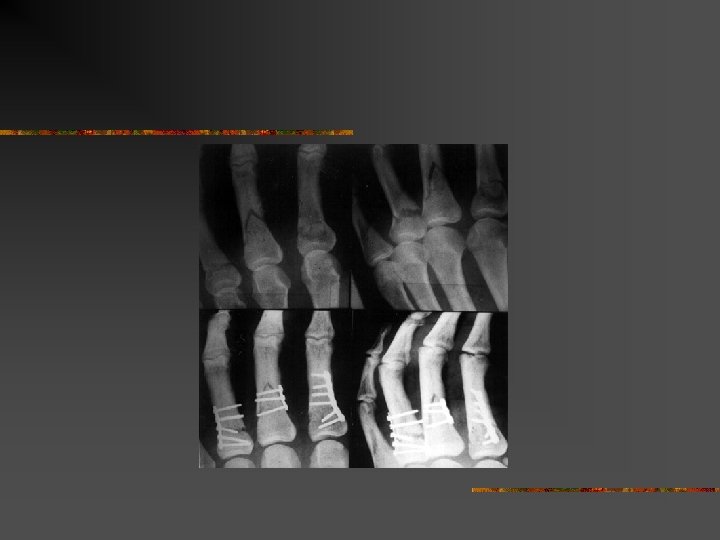

Homme 16 ans. Traumatisme des deux mains par bombe artisanale

Homme 16 ans. traumatisme des deux mains par bombe artisanale amputation à gauche et lambeau IOP à droite

Homme de 61 ans. Traumatisme index droit par pétard à taupe. Dévascularisation. Revascularisation par pontage veineux

Au total n n Gravités des lésions Patients jeunes Consolidation moyenne de 28 semaines Sur 24 patients : n n n 1 amputation bilatérale en avant bras 1 amputation de la main 8 mains séquellaires graves : 5 mains sans pouce n 1 pouce sans main n 2 mains figées n

Traitement : n En urgences : n n Entre J 3 et J 5 : n n n Parage Stabilisation des lésions osseuses Revascularisation Parage secondaire Couverture Prévention +++